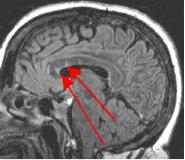

Thin-section sagittal FLAIR images increase detection of small MS plaques even further, first reported by Hashemi, et al. (Ref. 1). They also have the advantage of clearly showing the corpus callosum and subependymal regions. An early sign of MS is subependymal nodularity and subcallosal striations (Ref. 1-2), not clearly visible on axial images. Fig. 3-4 in the same patient clearly show subcallosal MS plaques (arrows) along the undersurface of corpus callosum.